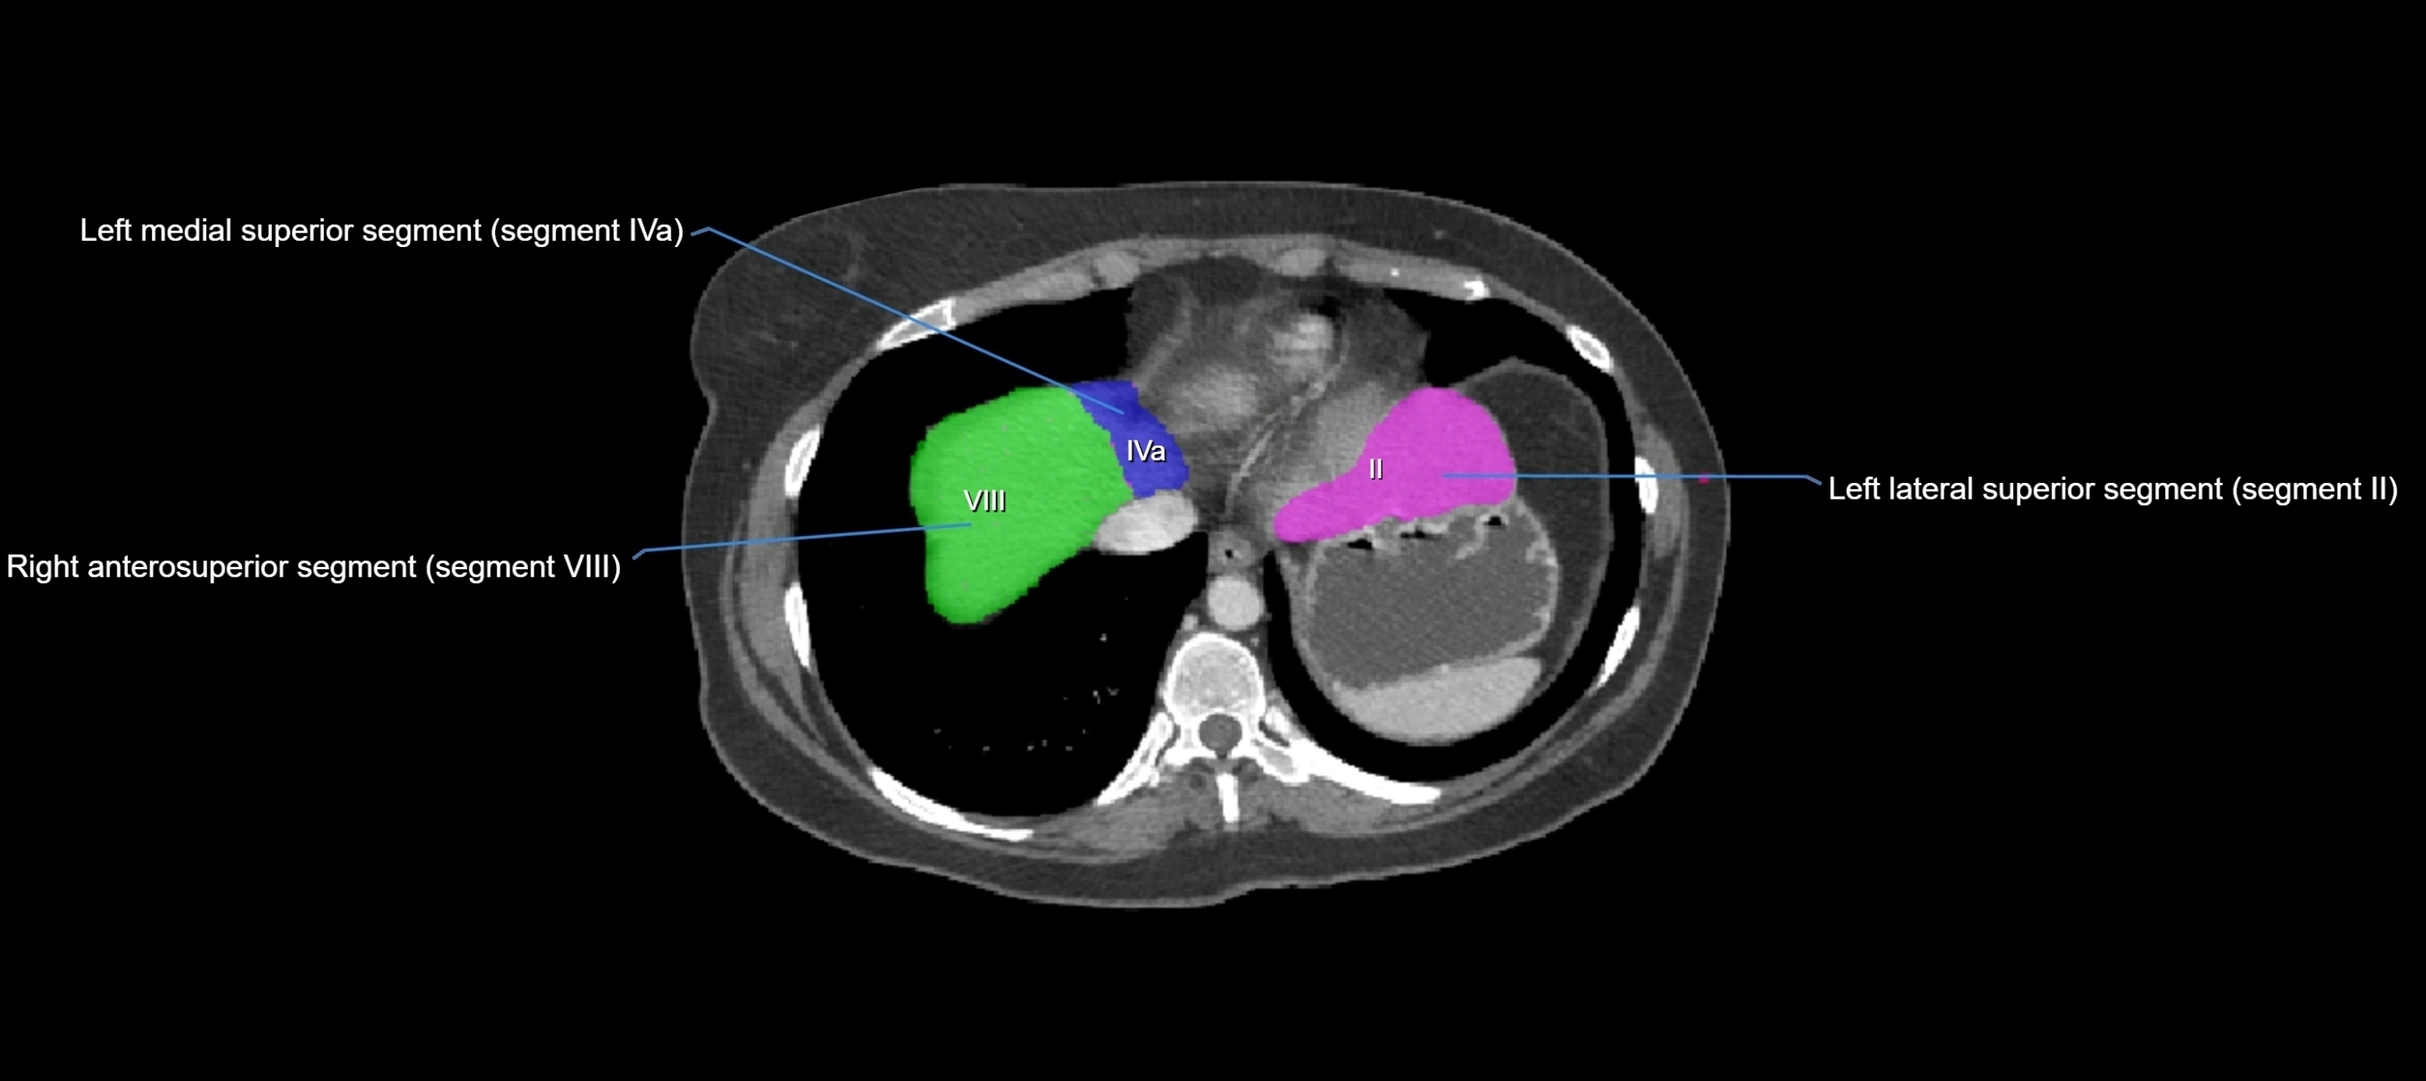

CT Image

image